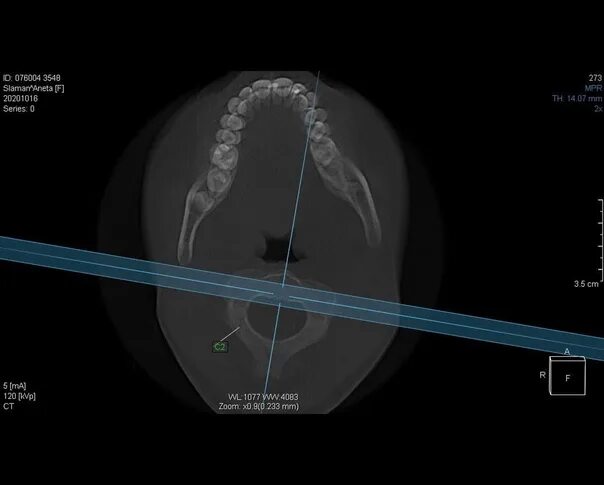

Атлант кт